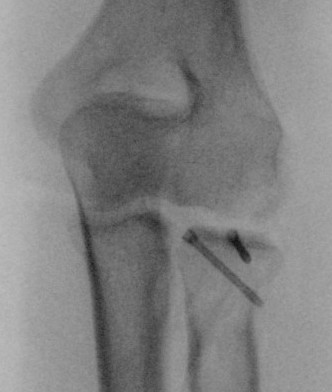

Radial Head Fixation

Indication

Significant fragment displacement

Reconstructable

Technique

Identify safe zone for implants

- posterolateral portion of cartilage / yellow and thinner, non articulating cartilage

- 90o arc between radial styloid and Lister's tubercle

- 2.5 or 3.5 headless compression screws